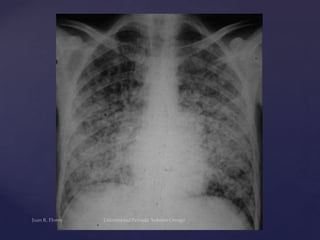

Histoplasmosis

Infiltrados pulmonares

bilaterales en los

campos medios,

superpuestos a los

hilios.

Histoplasmosis Infiltrados pulmonares bilaterales enlos campos medios, superpuestos a los hilios.